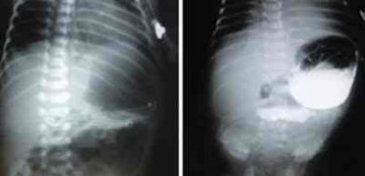

Estenosis hipertrófica de píloro

El estómago conecta el esófago con el intestino delgado. El píloro es un esfínter muscular delgado y estrecho a través del cual el alimento pasa al duodeno después de haber sido parcialmente digerido en el estómago.

Diagnóstico